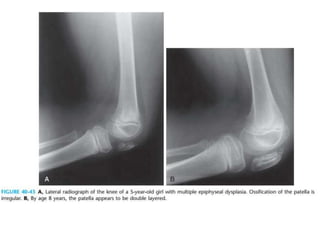

• Double-layered patella in the lateral view

• In thegrowing patient,the epiphyses are fragmented and small in size • In adulthood, major joints develop premature osteoarthritis • Femoral condyles are flattened • Double-layered patella in the lateral view • hatchet head of humerus